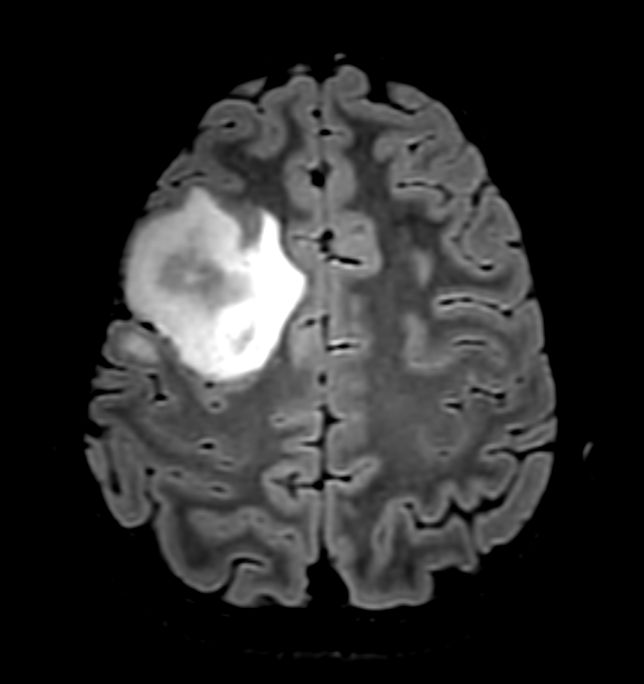

Diffusion (b1000)

Patient with a brain lesion. ExamCard includes MultiVane XD for motion-free imaging in short scan time, Compressed SENSE to shorten exam time, SWIp to enhance contrast for deoxygenated (venous) blood or calcium deposits, a high resolution 3D FLAIR sequence enabling reformats in any plane without loss of resolution, diffusion to achieve high contrast between background and lesions, pCASL to visualize brain perfusion and functional physiology in a non-contrast manner, dynamic multi-slice T2* perfusion for quantitative analysis, and spectroscopy for a non-invasive measurement of biochemical changes in the brain.